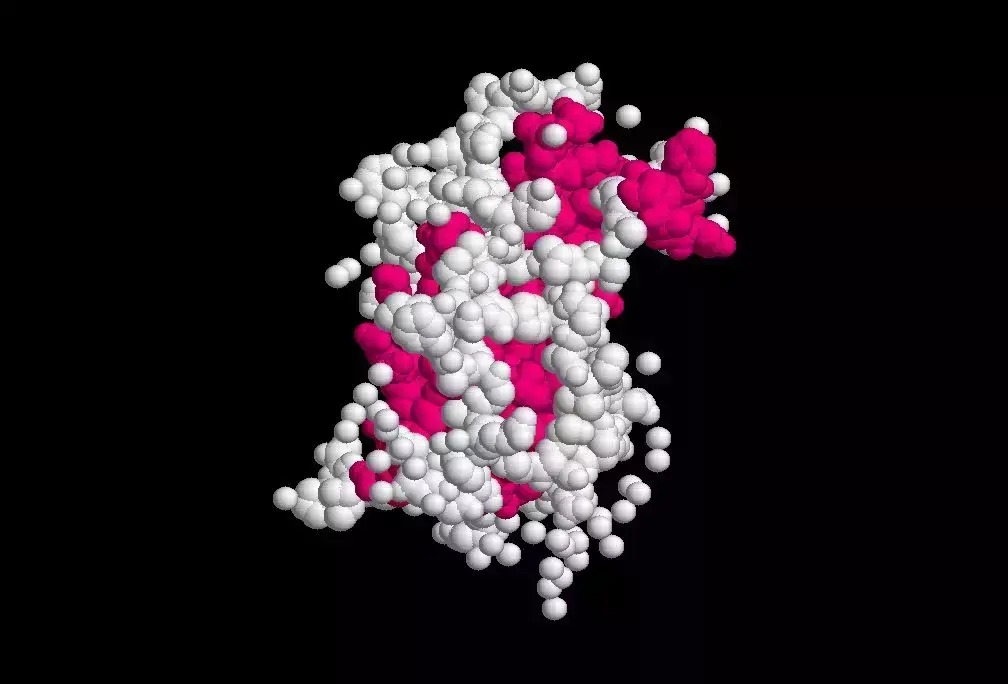

垂体又称为“脑下垂体”,是大脑底部水滴状下垂的结构。

只有一粒豌豆那么大,但它却能分泌出与人类身体生长最密切相关的激素——生长激素(growth hormone)。

其功能包括促进身体组织的生长,使体内细胞的数目增加及变大,使身体各部分组织器官变大等。

若脑下垂体发生异常,就有可能引发生长激素的分泌异常。

分泌过少,会引发侏儒症。分泌过多,则会引发巨人症。

生长激素

其中,引发生长激素分泌过旺的最常见原因,便是脑下垂体腺瘤。